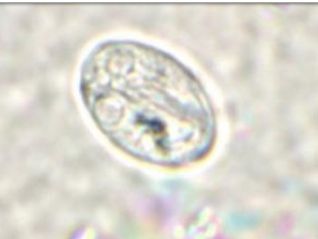

วัดความรู้ว่ารู้จักไข่พยาธิแค่ไหน